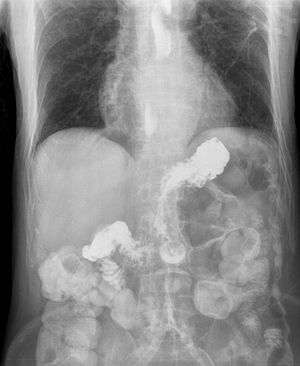

X-ray showing radiocontrast from the stomach entering the esophagus due to severe reflux | |